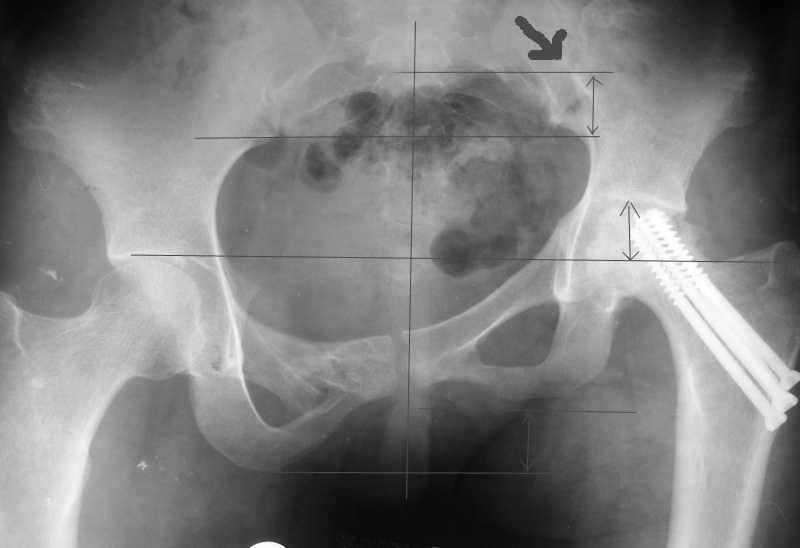

Привет, Макс. Не торопись, посмотри внимательно на истинную картину. Толстая стрелка указывает на нижний край смещенного кп сочленения.

Поэтому считаю, что Принять какое-либо решение без кт и дополнительных проекций неразумно.

Доброго времени суток. Согласен с предыдущими авторами, что необходимы стандартные проекции рентгенограмм и КТ (желательно с 3D). Обратите внимание, что рентгенограммы получились с небольшим поворотом вправо (по естественным причинам) и косо. Последнее можно скорректировать поворотом изображения по часовой стрелке на 2,6 градусов (для большей наглядности).

Вероятнее всего, что укорочение конечности за счет таза составит не более 3 см.,

Это хорошо видно на прилагаемой картине